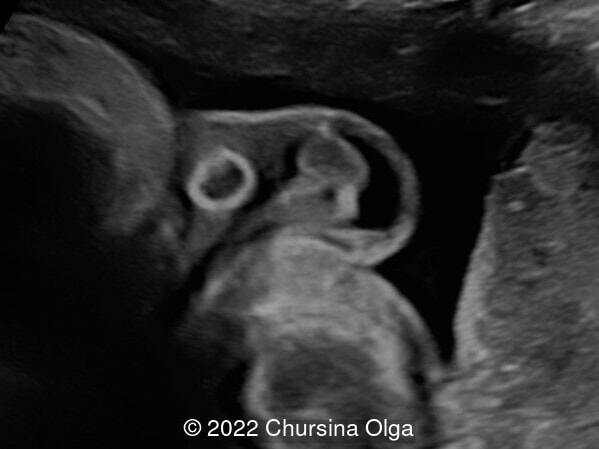

Our ultrasound examination revealed appropriate fetal growth, as well as normal amniotic fluid and placenta. Examination of the fetal scrotum showed a discrepancy in size between the right and left with the left side being smaller (Image 1). A rounded bean-shaped mass measuring 8.8 x 4.6 mm with a thick, hyperechogenic fibrous contour was detected in the left half of the scrotum. The normal structure of the left testis is not detected. The right fetal testis was normal (Image 2). On doppler imaging, there is absence of flow in the left hemiscrotum, and normal flow on the right side (Image 3). The left testicular appendages are not visualized. On dynamic observation, there is no peristaltic movement in the left half of the scrotum. The right scrotum shows a normal testicular structure with appendages. There is no hydrocele in the scrotum (Image 3).

• Image 2: Bean-shaped formation of the left half of the fetal scrotum, the right testicle is normal